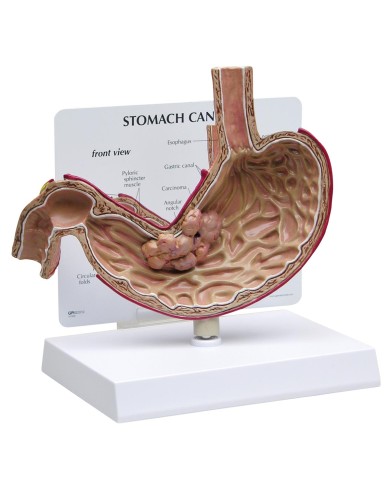

I Modelli anatomici 3B scientific ed Erler Zimmer sono quanto di meglio esista per studiare l'anatomia del corpo umano, il catalogo dei modelli anatomici comprende modelli di cranio, scomponibili, colorati, crani anatomici, crani su cavalletto, e il modello di punta, il cranio in 22 parti, ad incastro magnetico.

I modelli anatomici didattici sono riproduzioni di strutture anatomiche perfettamente uguali a quelle vere, i modelli di ossa sono realizzati dalla scansione di ossa vere, l'esperienza tattile è assolutamente realistica, ed anche il peso delle ossa corrisponde all'incirca al peso delle ossa vere.

Sono indispensabili per lo studio dell'anatomia umana, oggi è possibile osservare le strutture anatomiche senza la necessità di dissezionare cadaveri o di effettuare studi pericolosi su pazienti vivi.

Gli studenti di medicina utilizzano i modelli anatomici per i loro studi di anatomia umana, studiare l'anatomia sui libri non basta, un modellino anatomico permette uno studio molto più accurato che una foto o un disegno su un libro.

Medici, fisioterapisti, osteopati e professionisti sanitari utilizzano i modelli anatomici per dare spiegazioni ai pazienti sulle patologie, risparmiando tanto tempo prezioso durante la spiegazione, che diventa molto più efficace.